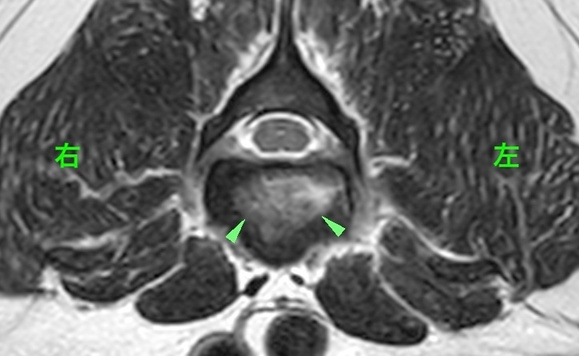

<症例情報> ウェルシュ・コーギー10歳 去勢雄 【主訴】数ヶ月前から後ろ足の進行性麻痺を認めた→MRI検査を実施 …